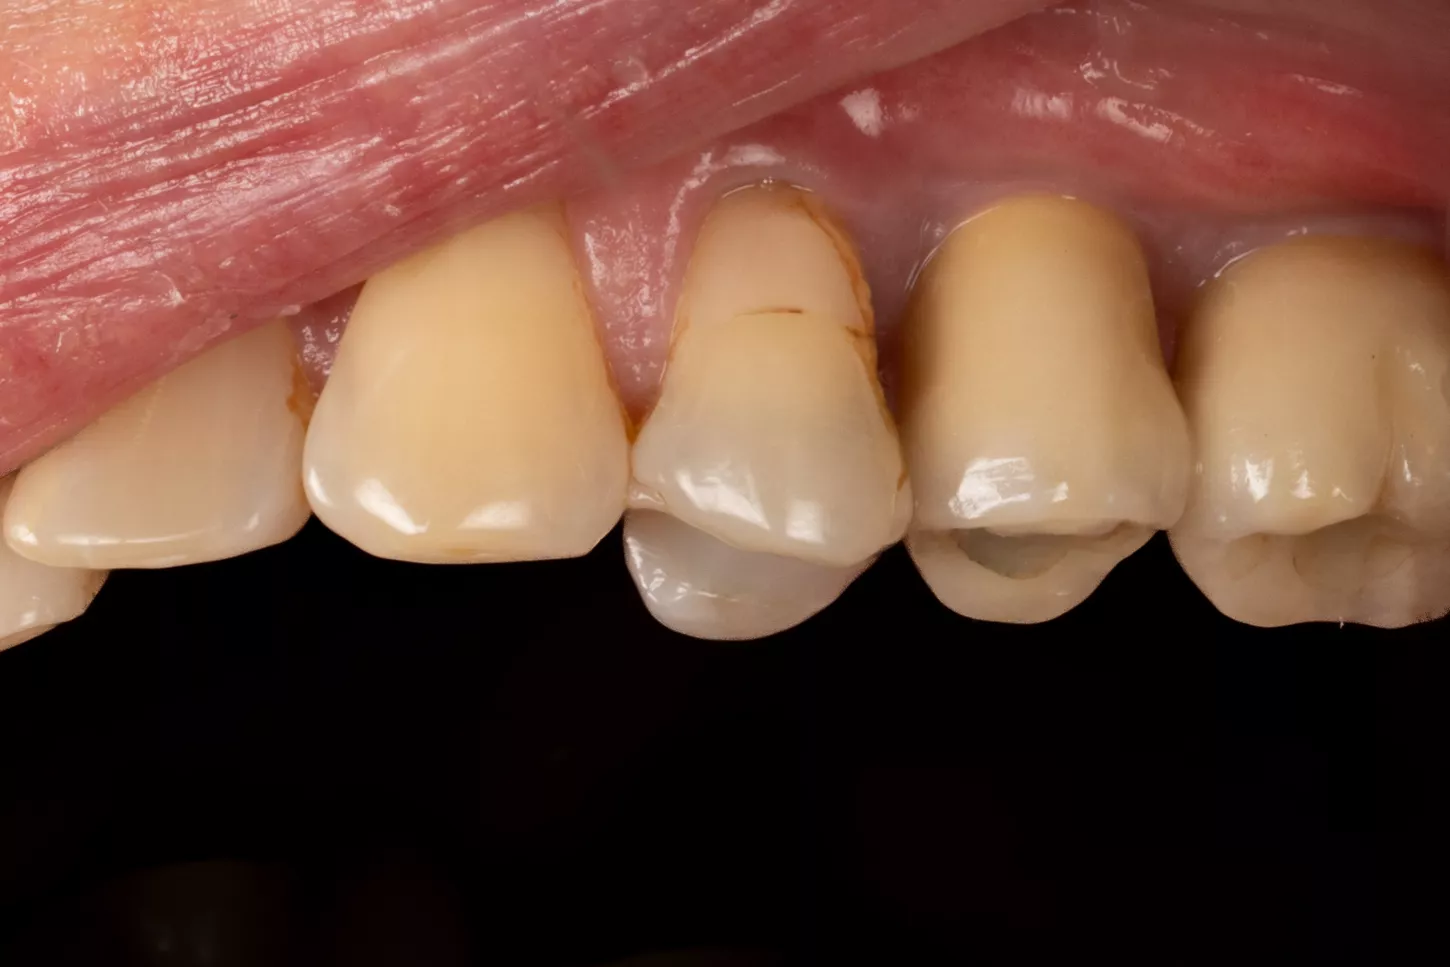

3a-b & 4a-b. Preoperative situation.

Free-end saddle. Periodontal tissue appeared healthy. Plenty of keratinized tissue. Notice the more extensive vestibular bone loss around 25.

19. Final prosthesis in the mouth 3 years post implant placement.